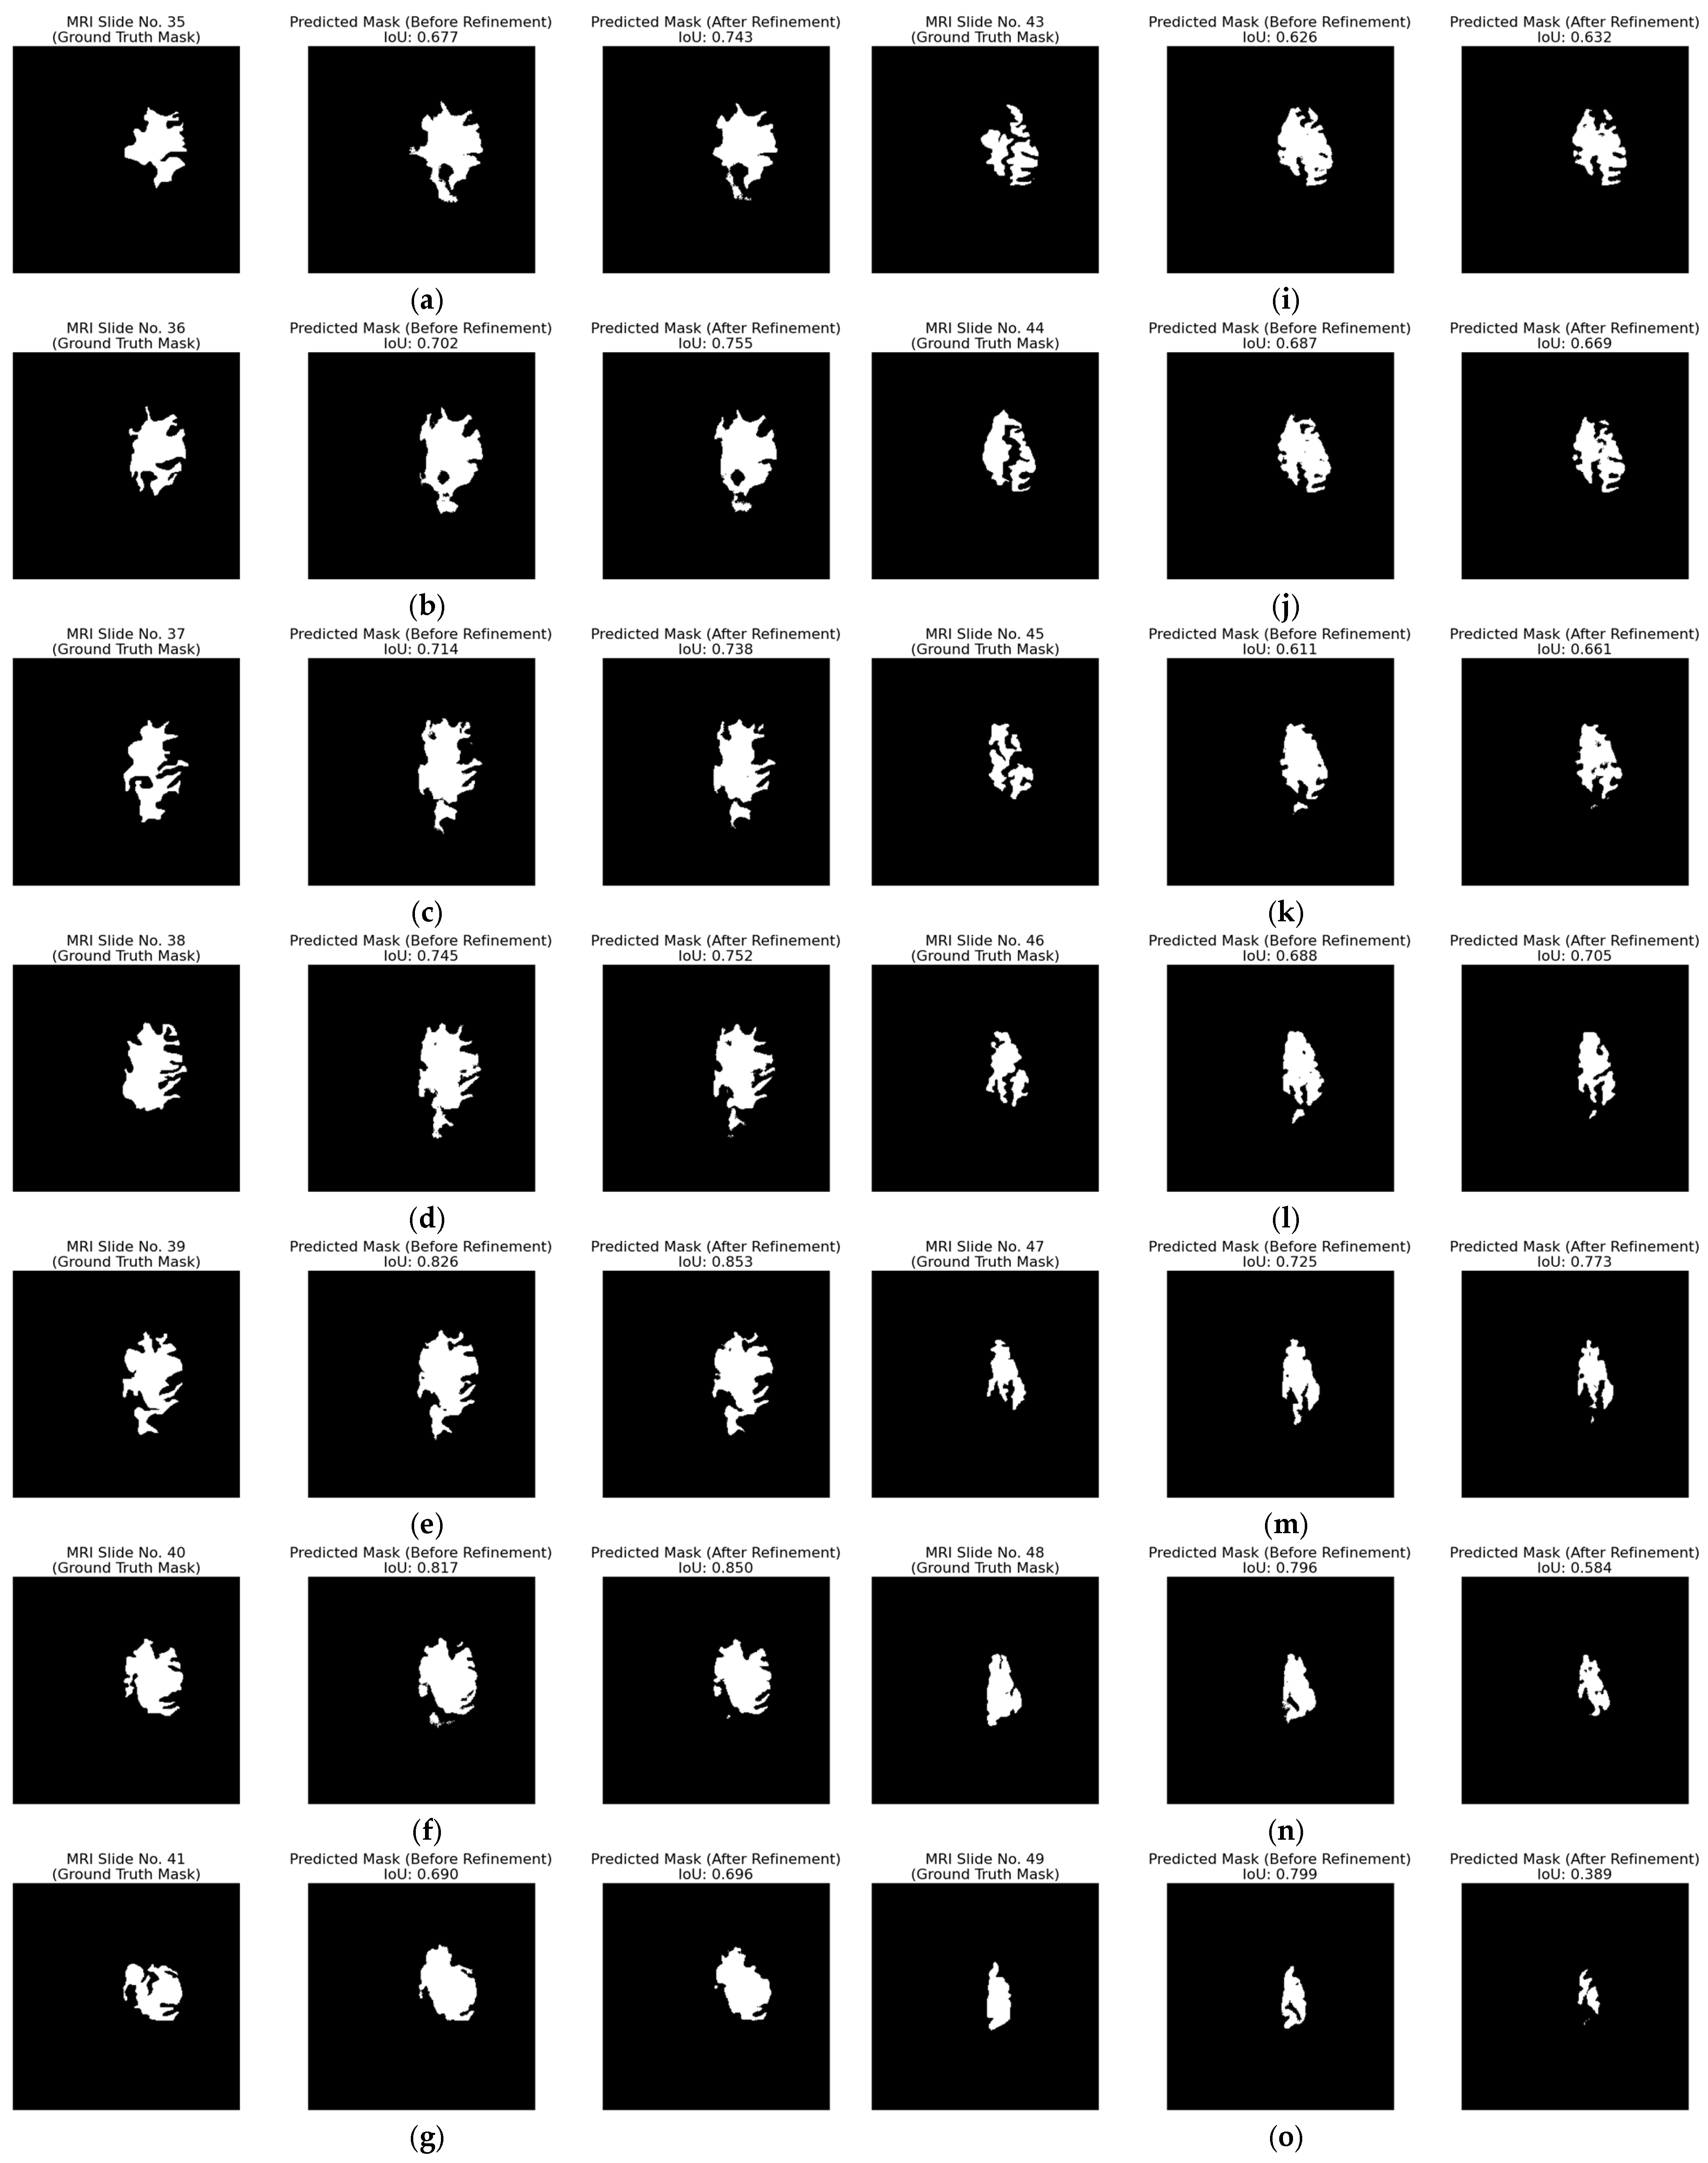

4.2. Qualitative Results

| Inaccurate segmentation | Figure 14 | Fragmented or under-segmented predictions, especially for complex tumor morphologies | 0.599, 0.598, 0.378 |